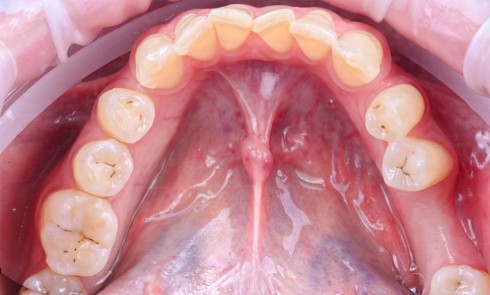

Une patiente de 64 ans, en bonne santé générale, suivie en maintenance parodontale depuis sept ans (parodontite 3B), est vue en juin 2014 pour l’extraction de sa 24 en raison d’infections endodontiques récurrentes. Le plan de traitement prévoit la pose extemporanée d’un implant et sa restauration prothétique quatre mois plus tard. La 25 est une dent couronnée et 23 et 26 sont des restaurations implantaires (fig. 1a à c). La dent antagoniste 35 est une restauration implantaire.

En mars 2016, la patiente se plaint d’une sensibilité sur la 25 et on note cliniquement une inflammation gingivale associée à un décalage apical du rebord marginal et de la ligne muco-gingivale en comparaison de leur situation visualisée au niveau des coiffes supra-implantaires. La couronne clinique est réduite et une infraposition avec une inocclusion d’environ 2 mm par rapport au plan d’occlusion et aux dents antagonistes est également notée (fig. 2 à 4). Un saignement au sondage ainsi qu’une poche de 5 mm en distal sont constatés. Le test de percussion est positif. Les tissus péri-implantaires adjacents ne présentent aucun signe de mucosite.